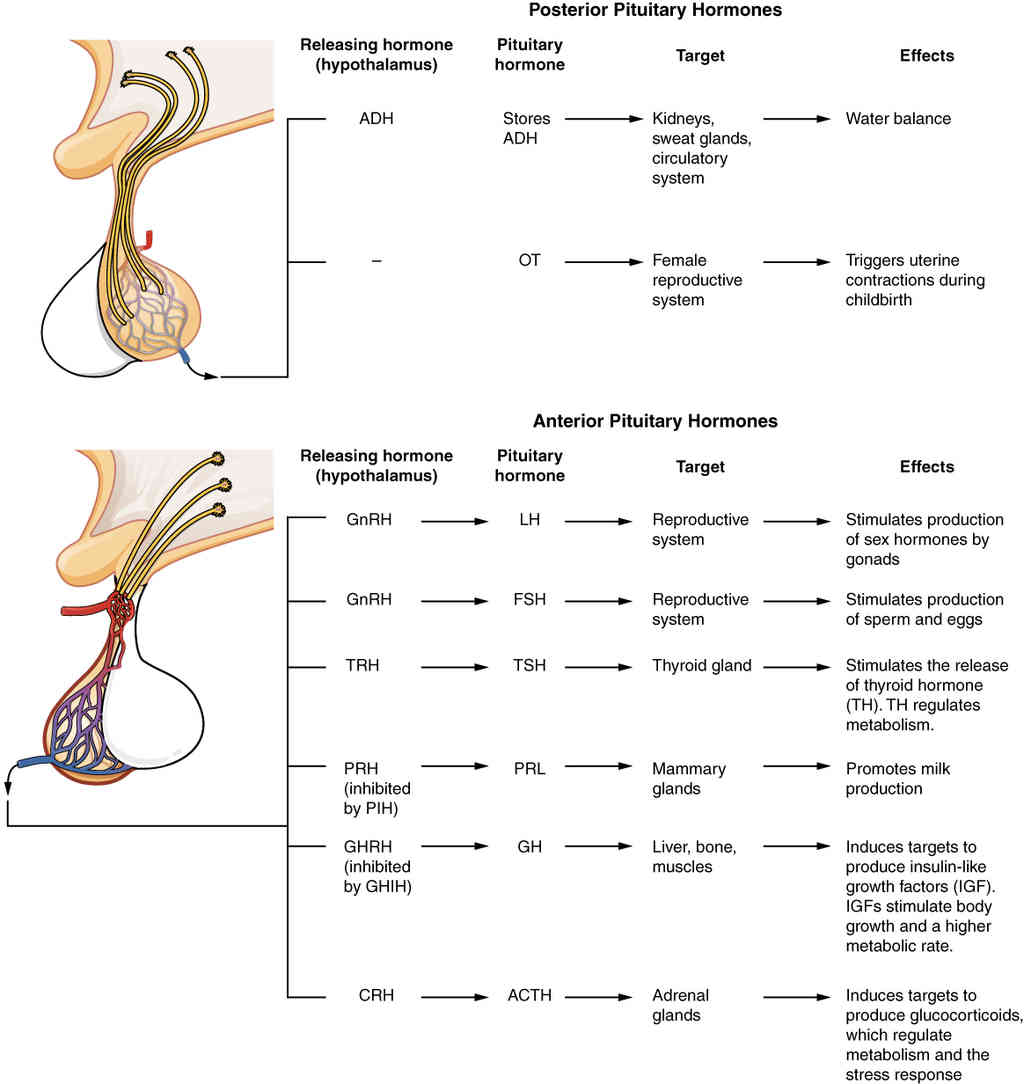

This page is under construction. For now, it is just a resource of the images found in the OpenStax Anatomy and Physiology Handbook. It wil slowly change into a revision tool. Each slide has a number. Use this to refer to the slide. When completed, it will have an unlabelled section, with labelled slides in parallel. On the unlabelled slides, write your answer and use the labelled slide to assess yourself. Keep track by also noting the number on each slide. Improvement at each attempt is important, more so than full marks on a first attempt.